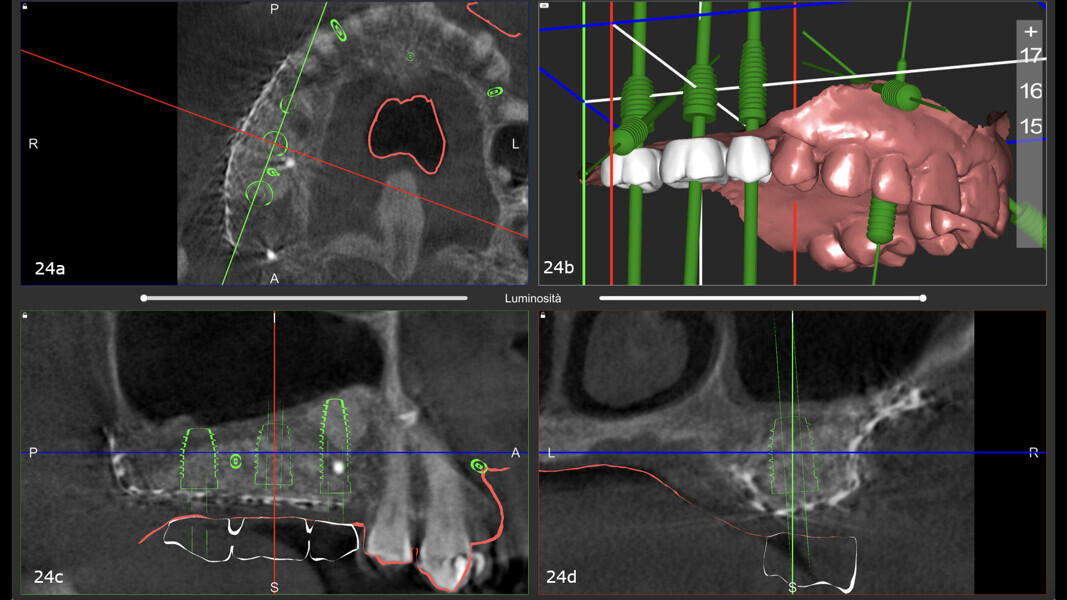

After nine months, a second CBCT scan was performed to assess the regenerated bone volume and plan the computer-guided surgery (Figa. 23a-f). The STL files obtained from the intra-oral scan, and the DICOM files from the CBCT scan were used to plan implant placement through computer-guided surgery (naviMAX, Biomax; Figs. 24a-d).